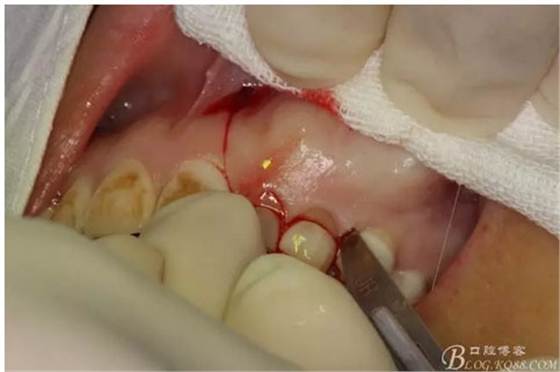

圖7.行左側(cè)乳Ⅱ近中唇側(cè)垂直切口,切透粘骨膜。

圖8. 沿左側(cè)乳Ⅱ、Ⅲ唇側(cè)齦溝內(nèi)切口至24部位。

圖9.從兩個切口的連接處開始翻瓣。全厚瓣。